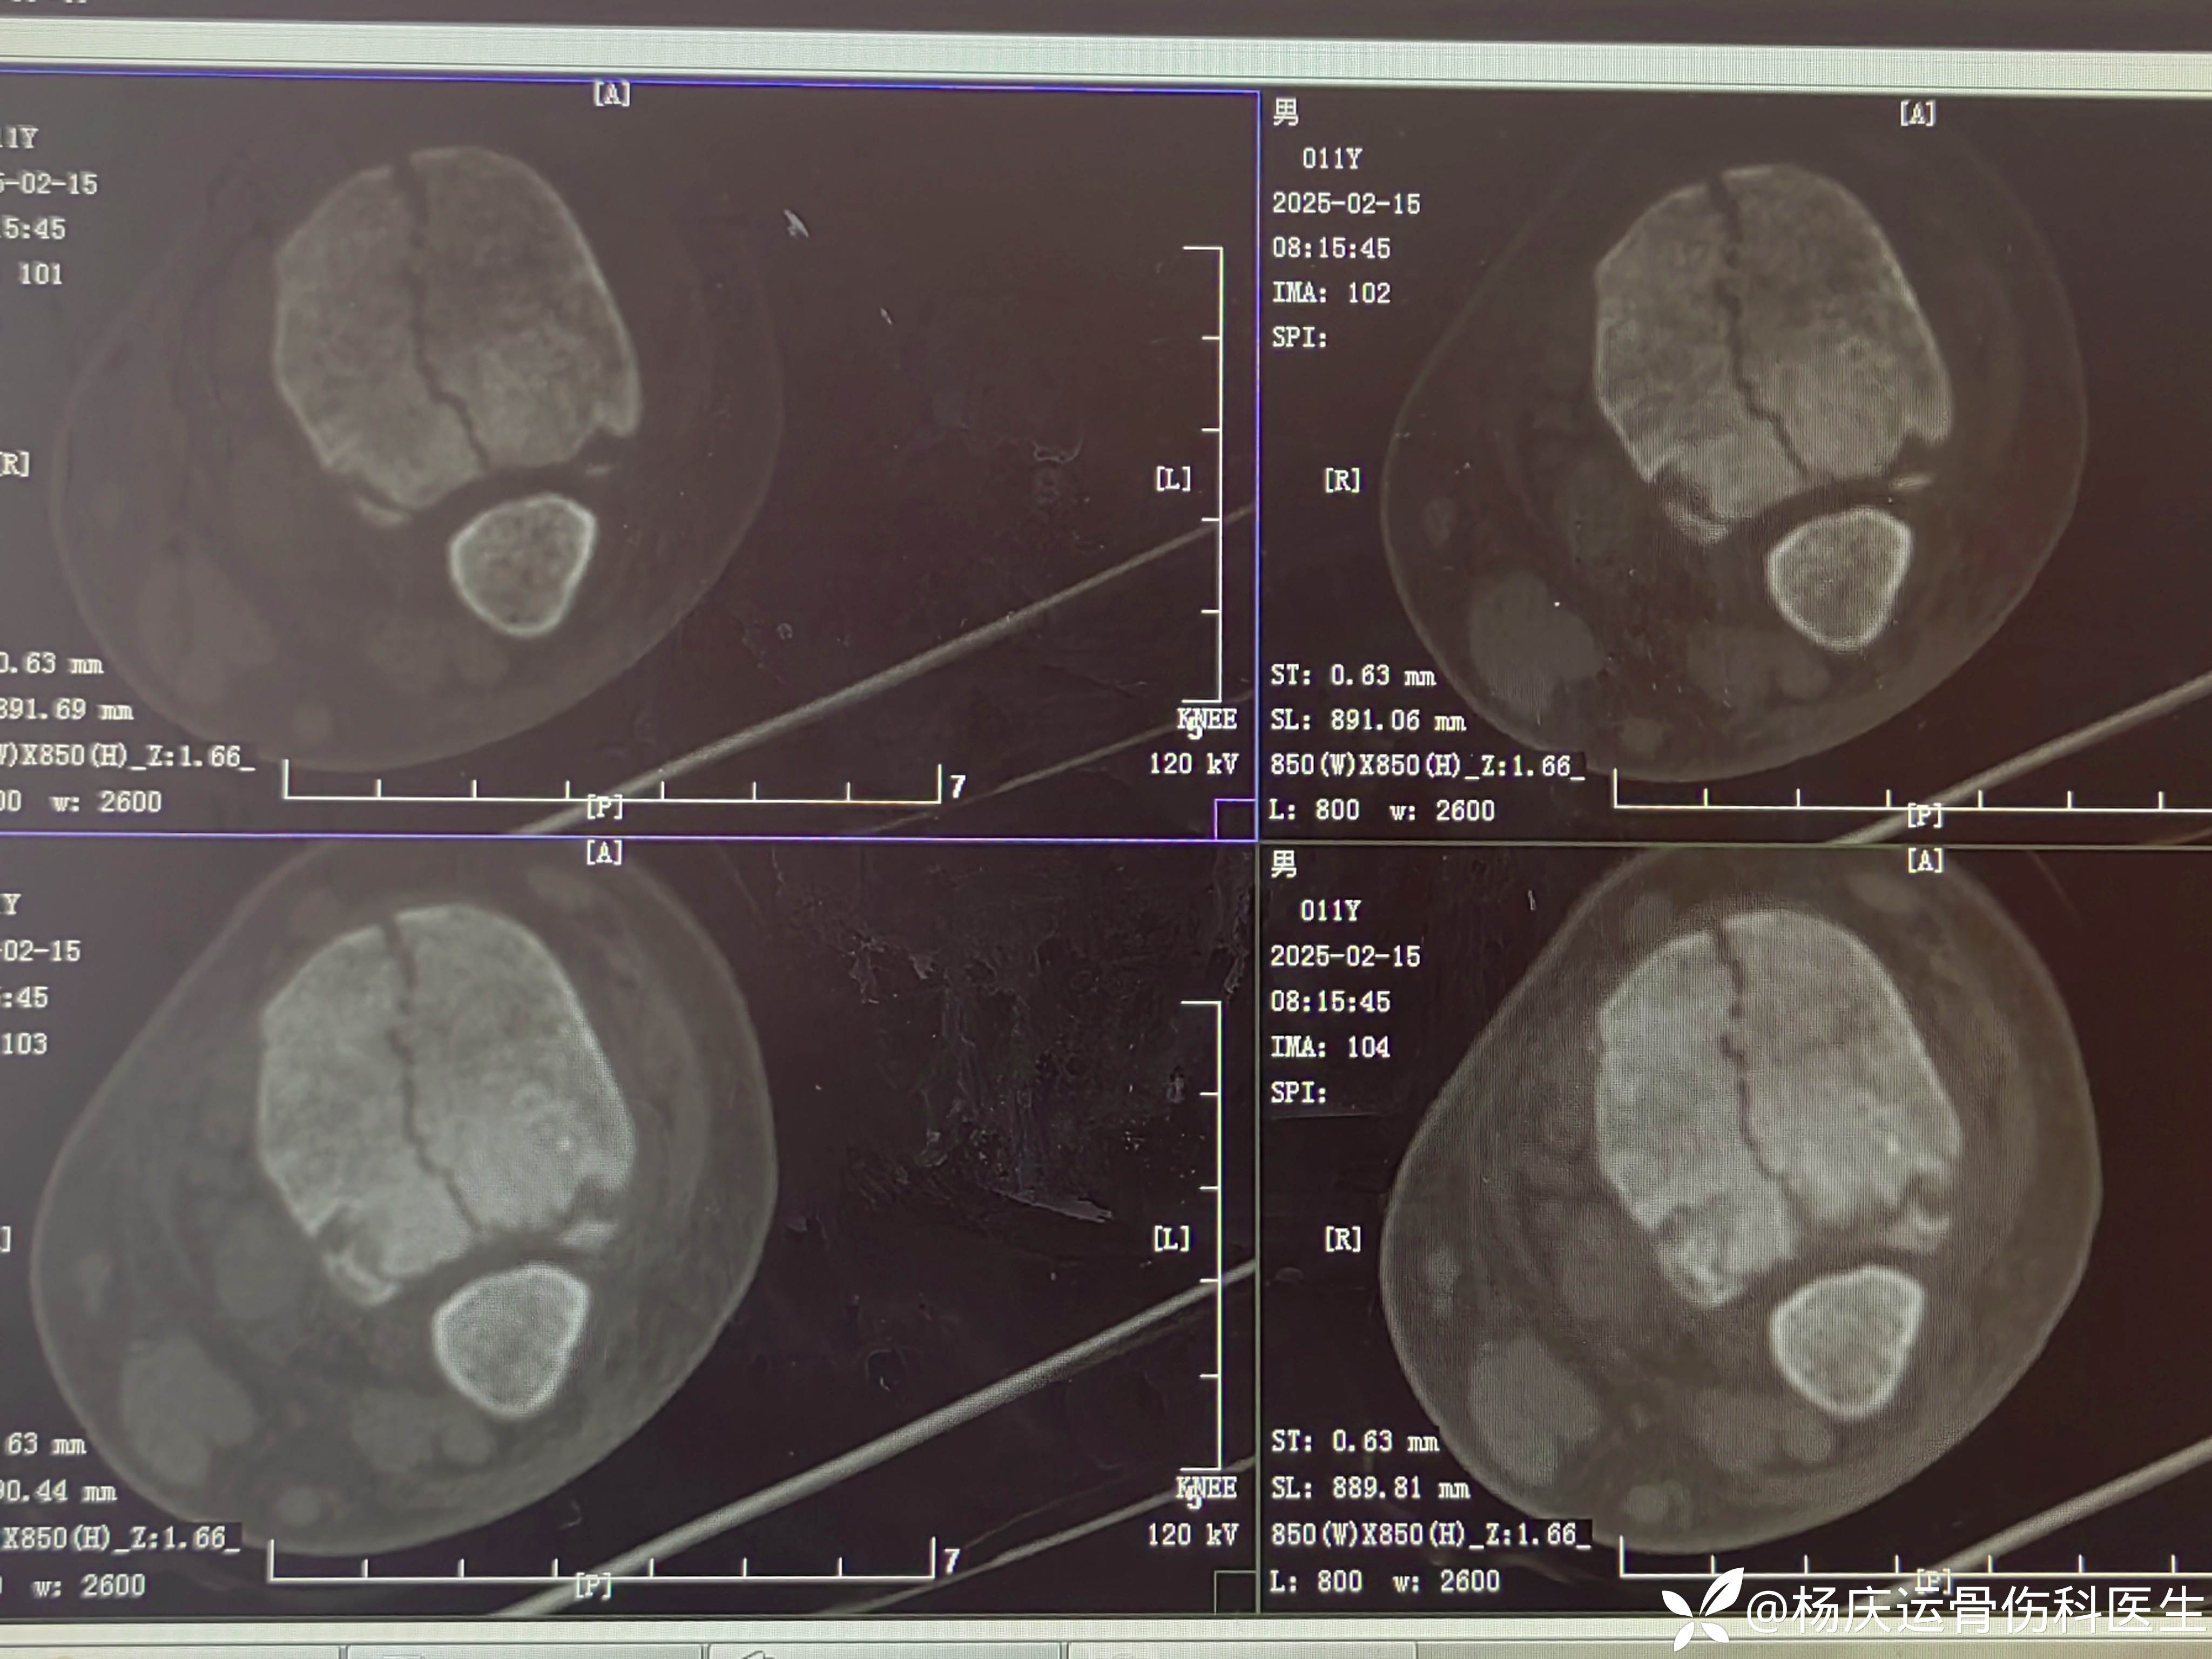

MRI显示骨折间隙仍大

再次复位后CT,断端间隙1.0mm(符合保守治疗标准<2mm)